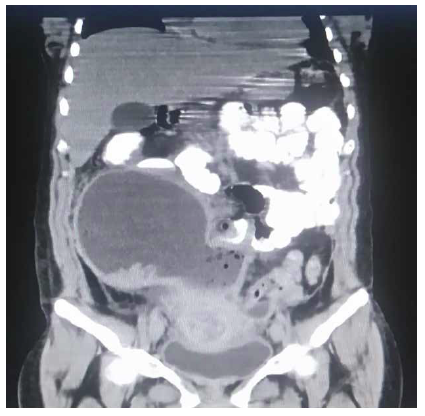

Se solicita una tomografía abdominal que revela una gran colección intraabdominal en el hemiabdomen derecho (Figura 1); se decide la laparoscopía exploratoria en la que se encuentra un absceso gigante intraabdominal de 750 cc (Figuras 2 y 3), que va desde el reborde inferior del hígado hasta el fondo de saco de Douglas. Se toma muestra para cultivo y se drena. Un útero aumentado de tamaño con fibrina en sus paredes, edema y eritema severo en la trompa derecha, revisando con azul de metileno para verificar su permeabilidad. Se encuentra el apéndice cecal en fase necrosada y perforada (Figura 4), el cual se extrae. Posteriormente se realiza el lavado peritoneal con 6.000 cc de solución salina normal (Figura 5). Se deja drenaje en fondo de saco de Douglas (Figura 6). El tiempo de hospitalización y el manejo antibiótico con piperacilina tazobactam fue de 10 días. El reporte del cultivo fue Escherichia coli.